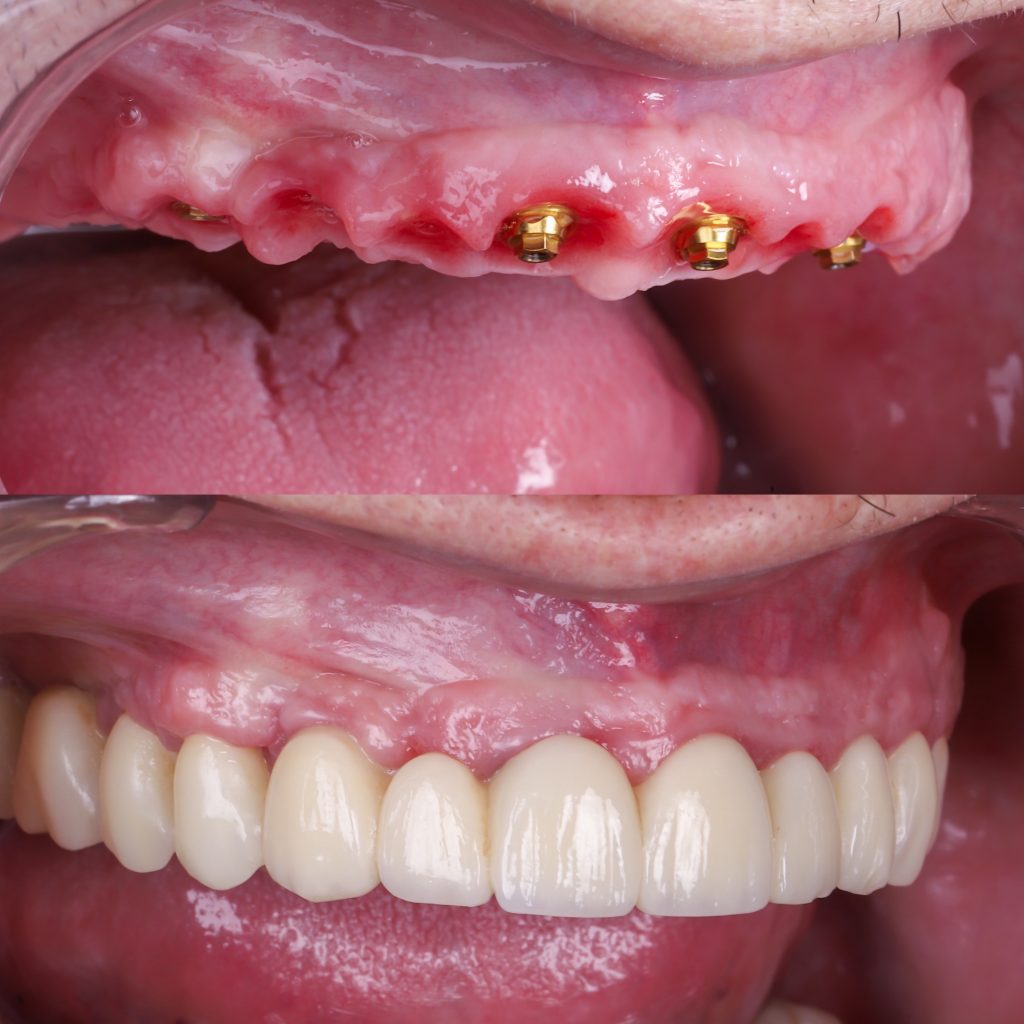

Permiten colocar dientes fijos en 24 horas mediante la técnica carga inmediata.

Estética inmediata gracias a la prótesis provisional realizada por nuestro laboratorio en exclusiva.

La mayoría de los pacientes destacan que en otras clínicas les dijeron que no tenían hueso suficiente para ponerse implantes, pero en Alejandro Prieto Dental encontraron por fin una solución. Comentan que la cirugía fue mucho más cómoda y rápida de lo que esperaban y que poder salir con dientes fijos el mismo día les cambió la experiencia por completo.

Muchos señalan que han recuperado la confianza, la masticación y una estética totalmente natural, algo que no creían posible. Además, valoran especialmente la tecnología digital utilizada, la precisión en la planificación y el trato cercano del equipo, y coinciden en que el resultado final ha superado con creces lo que imaginaban.

Antes y después